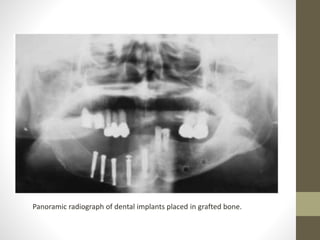

• One year and 7 months after the reconstruction, five 3.75 X

mandible

Panoramic radiograph of dental implants placed in grafted bone.